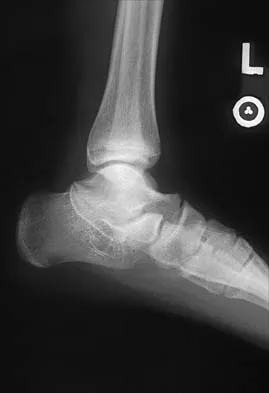

A 57-year-old man has had right ankle pain for the past 10 months following an injury that went untreated. Radiographs are shown in Figures 30a through 30c. Management should consist of

Explanation

The radiographs reveal a malunited distal fibular fracture with shortening. Because there appears to be an adequate cartilage space within the ankle joint, the role of reconstruction would be to prevent arthrosis and the need for ankle arthrodesis, as well as to decrease symptoms. The treatment of choice is restoration of fibular length, alignment, and rotation with osteotomy plating, and bone grafting as needed. There is no indication for ligament reconstruction of a mechanically stable ankle, and tibial shortening osteotomy will not assist in correcting the deformity. Cast immobilization may assist with improvement of symptoms but will not correct the overall process. Determination of fibular length is best done by comparing the talocrural angle of the injured side with the uninjured side. The goal is to perfectly reduce the talus in the ankle mortise. Marti RK, Raaymakers EL, Nolte PA: Malunited ankle fractures: The late results of reconstruction. J Bone Joint Surg Br 1990;72:709-713. Geissler W, Tsao A, Hughes J: Fractures and injuries of the ankle, in Rockwood CA Jr, Green DP, Bucholz RW, Heckman JD (eds): Rockwood and Green's Fractures in Adults, ed 4. Philadelphia, PA, Lippincott-Raven, 1996, pp 2201-2206.